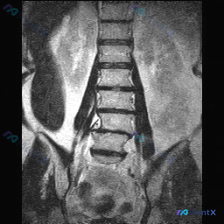

整理了一份腰椎MRI的影像资料,先放出来大家一起讨论。 核心影像表现(冠状位 T1 加权): 1. 腰椎序列存在轻度向左侧的代偿性弯曲 2. 下腰椎段(L4-L5 及 L5-S1)椎间隙明显狭窄,信号减低 3. 对应椎体边缘可见骨赘增生,伴骨质硬化或不规则改变 4. 小关节可见明显增生肥大,尤其是下...

网上看到一份标注为「脊柱侧凸」的腰椎MRI T1冠状位资料,整理了影像分析的核心信息,想和大家讨论一下。 目前的影像表现: - 腰椎各椎体(L1-L5)轮廓基本完整,无明显楔形变、压缩或骨质破坏 - 冠状位力线尚可,未见明显的侧弯畸形,椎间隙高度基本维持 - 双侧腰大肌对称,肌纤维信号未见明显异常,...